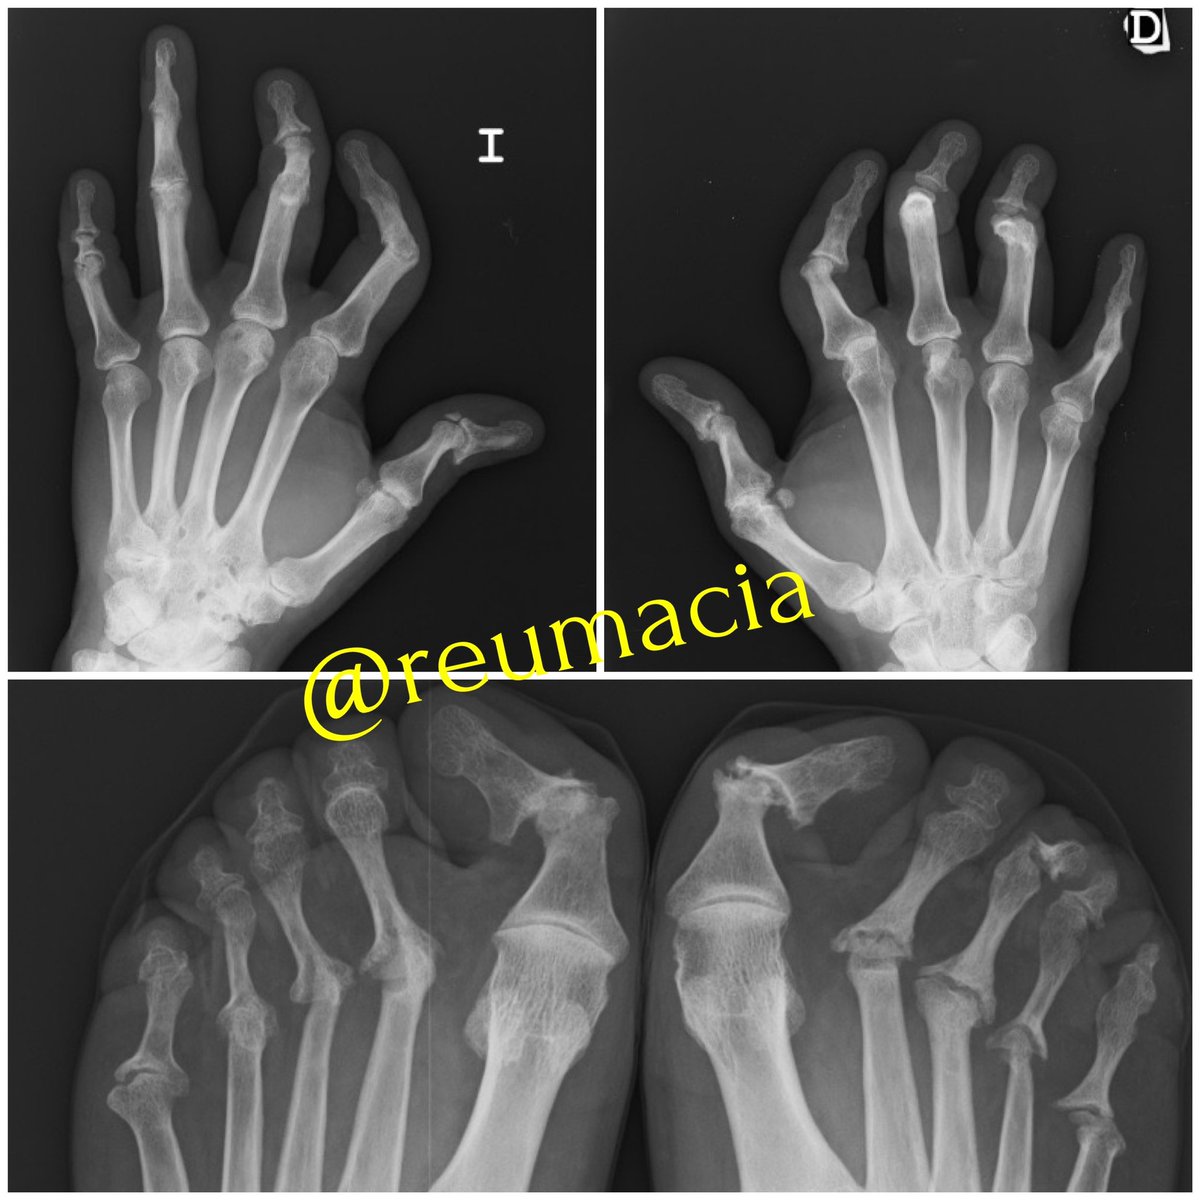

No os perdáis los preciosos dibujos-resumen de @reumatocita sobre enfermedades reumatológicas. ¡Más en su cuenta!